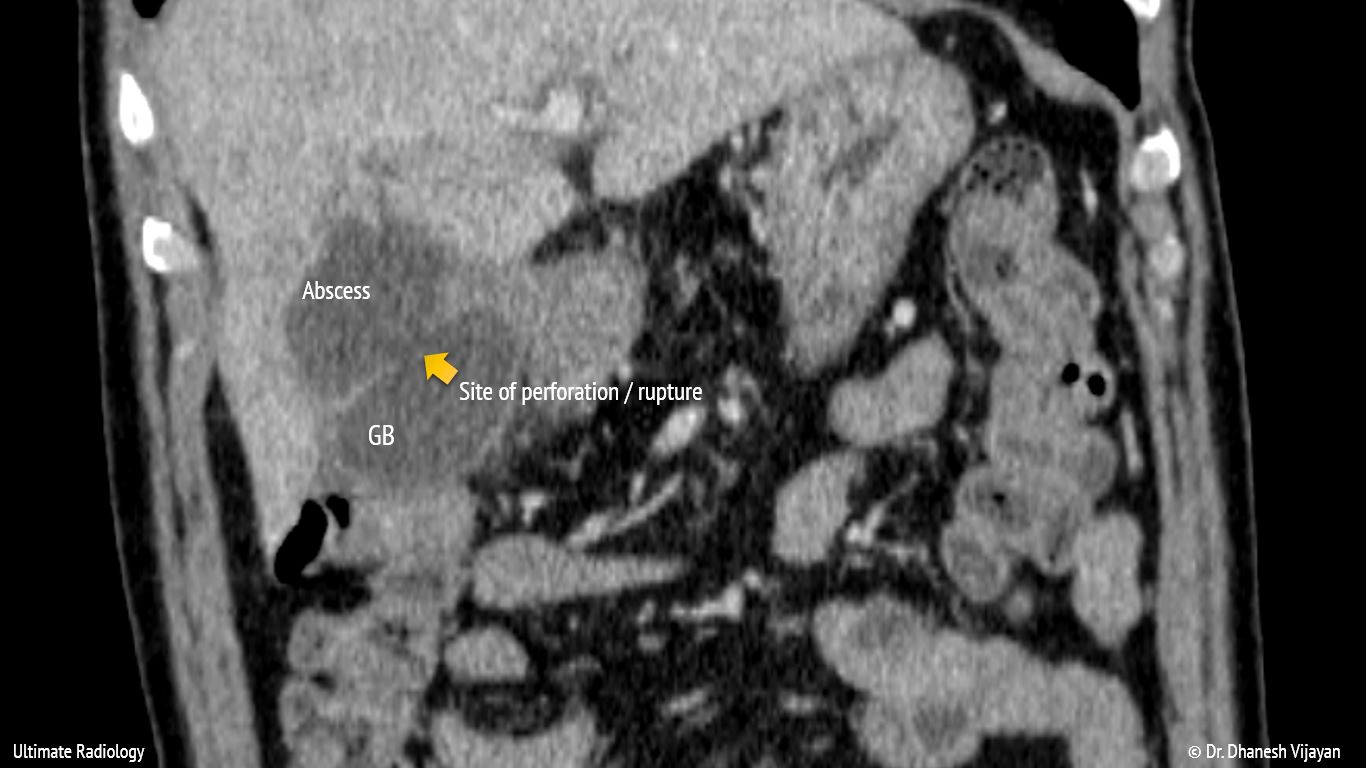

From ultimate-radiology.blogspot.com

Ultimate Radiology Acute Cholecystitis with intrahepatic perforation Abscess Rupture The rupture of pelvic abscess. List the treatment and management options. 1 abscesses are the result of an infection, generally. as some abscesses progress, they may point and come to a head so you can see the material inside and then. an abscess is a pocket of pus that forms within body tissues. when an abscess forms. Abscess Rupture.

Ultimate Radiology Acute Cholecystitis with intrahepatic perforation Abscess Rupture 1 abscesses are the result of an infection, generally. The rupture of pelvic abscess. an abscess is a pocket of pus that forms within body tissues. as some abscesses progress, they may point and come to a head so you can see the material inside and then. List the treatment and management options. when an abscess forms. Abscess Rupture.

Ultimate Radiology Acute Cholecystitis with intrahepatic perforation Abscess Rupture as some abscesses progress, they may point and come to a head so you can see the material inside and then. when an abscess forms under the skin, it forms a painful swollen lump with raised and inflamed edges, often with. 1 abscesses are the result of an infection, generally. The rupture of pelvic abscess. List the treatment. Abscess Rupture.